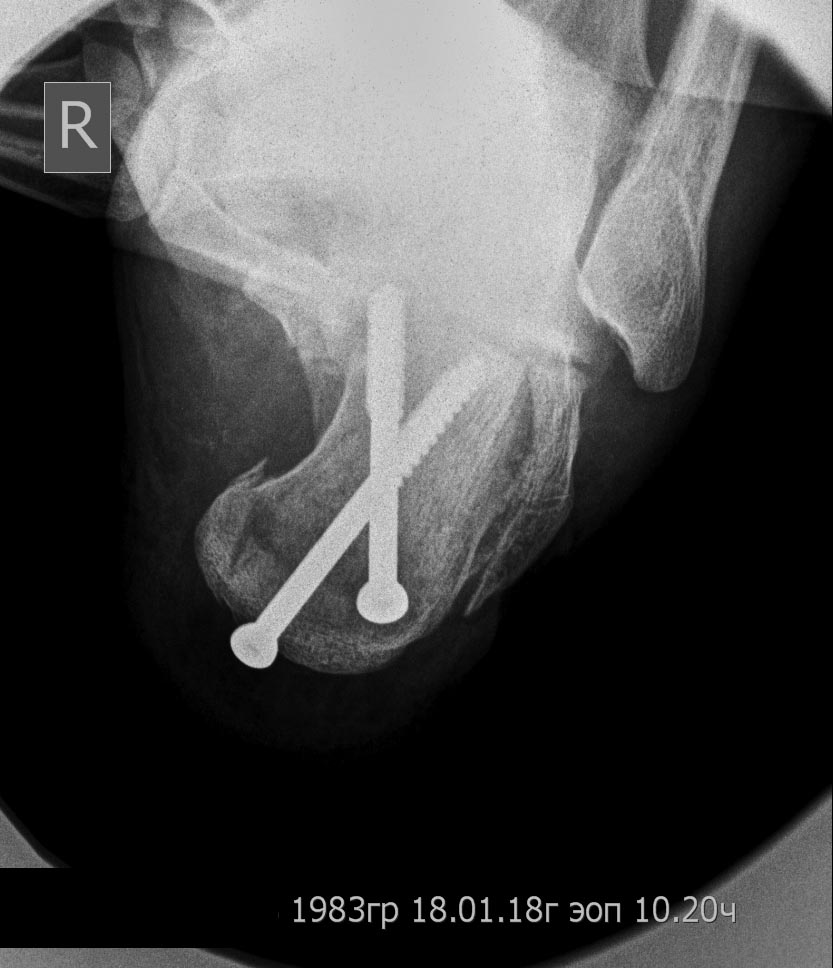

уважаемые коллеги ,помогите советом ,примерами.перелом пятки 4 мес назад

при дтп,синтез винтами.гипс носил около 3 мес ,нагрузка также через 3

мес(со слов пациента)в настоящий момент варусная деформация,толком

ходить на может,нагрузка на латеральну. полерхность пятки. латеральный

импиджмент.